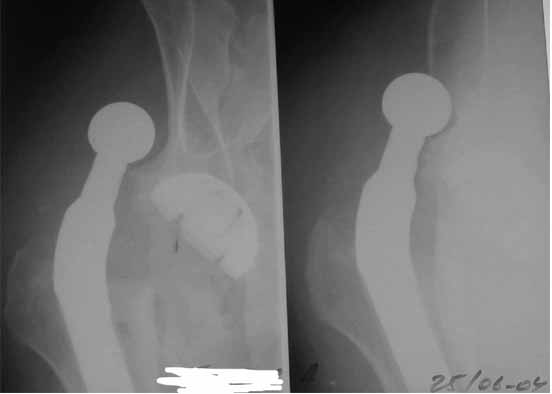

Во вложении - рентгенограммы после вывиха и после вправления.

Идея очень простая, в случае, если удасться прожить без вывиха 2.5-3 месяца, вероятность его возникновения в будущем значительно уменьшится. Оптимальный вариант - повторная иммобилизация на срок 6 недель с нагрузкой на ногу (как бы я ни не любил гипс, но этот путь проверенный и может дать результат). Если это невозможно, то исключительно осторожная реабилитация под строгим контролем без резких движений (спать в положении на спине с отведением и подушкой под коленкой и т.д.). Ходьба сама по себе не опасна, опасен переход от положения "лежа" в положение "полусидя" и "стоя" и наоборот.

Если все же вывих(и) повторятся, то другого выхода, кроме операции нет. Но к ней нужна супер серьезная материальная подготовка о которой я говорил раньше.